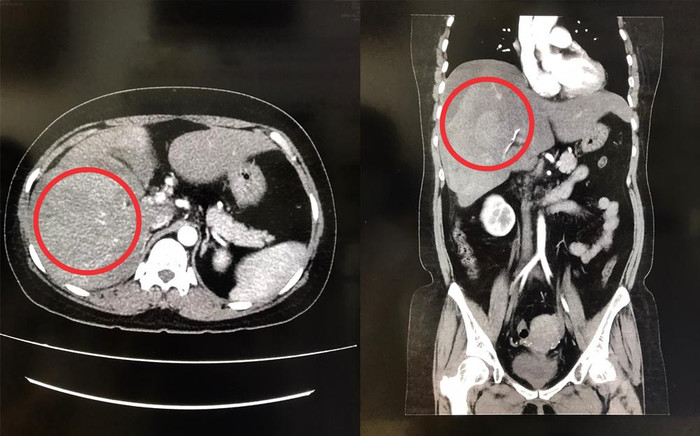

Ảnh chụp CT-scan cho thấy gan phải bị vỡ. (Ảnh: BVCC).

Đến rạng sáng 20/2, chị L. bất ngờ bị đau bụng dữ dội nên được người nhà đưa đến bệnh viện để điều trị. Qua thăm khám, bác sĩ chẩn đoán chị L. bị dập vỡ gan phải hạ phân thùy V, chảy máu ổ bụng, gây xuất huyết nội rất nguy hiểm.